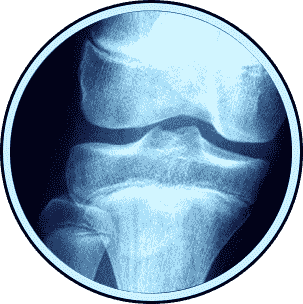

Are you experiencing hip discomfort that's limiting your daily activities? Before considering surgery, explore these non-surgical options that can provide relief and improve your quality of life.